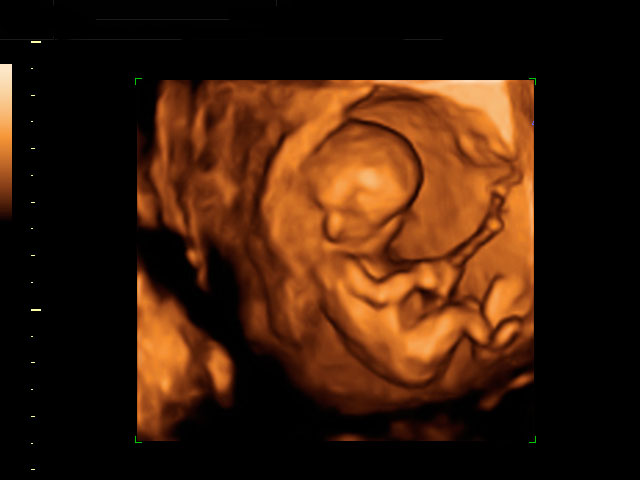

Ecografía Embarazo 4D - SEMANA 12